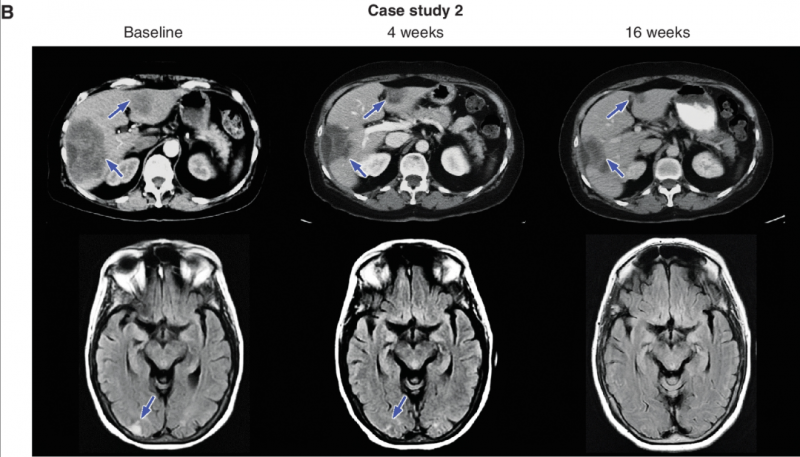

知名癌症杂志《cancer discovery》,报道了NVL-520在一例患IV期肺腺癌和多发性脑转移的65岁患者中,引发了客观肿瘤反应。该例患者循环肿瘤DNA(ctDNA)检测,发现了EZR-ROS1。在接受恩曲替尼(Entrectinib)治疗伊始,有初步反应,但 9 个月后病情出现进展。复查发现EZR-ROS1融合,并确定了ROS1 G2032R突变。患者随即开始接受卡铂、培美曲塞、贝伐珠单抗、恩曲替尼联合治疗。但不幸的是,效果不佳,患者脑转移不断增长,并出现了新的肝脏转移。患者在入组后,接受NVL-520治疗,结果显示:

1、在治疗第4周,肝脏和肺部的几个转移灶减少(根据RECIST 1.1,减少38%);右枕叶转移灶消退;EZR–ROS1和ROS1 G2032R等位基因频率降低。

2、在治疗5个月左右,患者达到部分缓解(PR),大脑和肝脏的疾病进一步消退(RECIST 1.1为-58%),且截止到数据统计时,未报告神经毒性(详见下图)。

图1 该患者接受NVL-520治疗前后,影像学对比图

①CT(上)图中的蓝色箭头,表示5/6段和3段肝转移,在治疗过程中持续消退。

②MRI(下)图中的蓝色箭头表示右枕叶转移,该转移在第4周时尺寸减小,并在第16周时变得几乎不可察觉。

综上,患有EZR-ROS1融合阳性肺腺癌,且具有ROS1 G2032R耐药突变的患者,在接受恩曲替尼(Entrectinib)和化疗后,证实对NVL-520有PR。